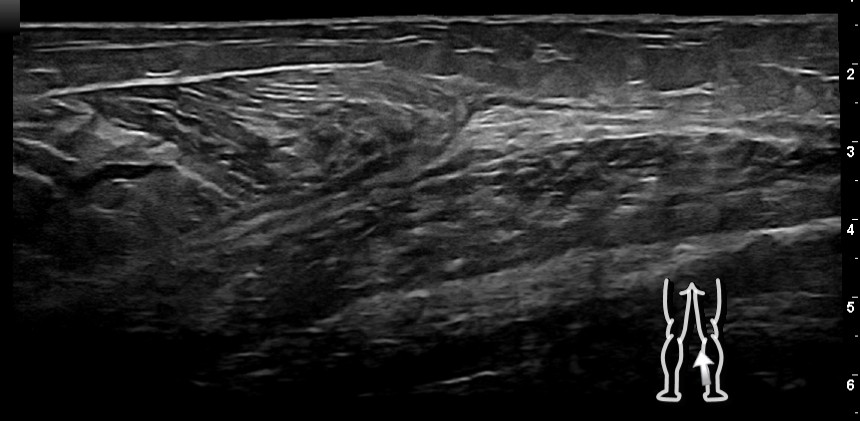

Hallazgos ecográficos

En cara posterior de pierna derecha, se observa, a nivel de la unión miotendinosa del gastrocnemio medial, una desorganización de las fibras musculares con pequeñas áreas anecogénicas compatibles con zonas de desgarro y hematoma.